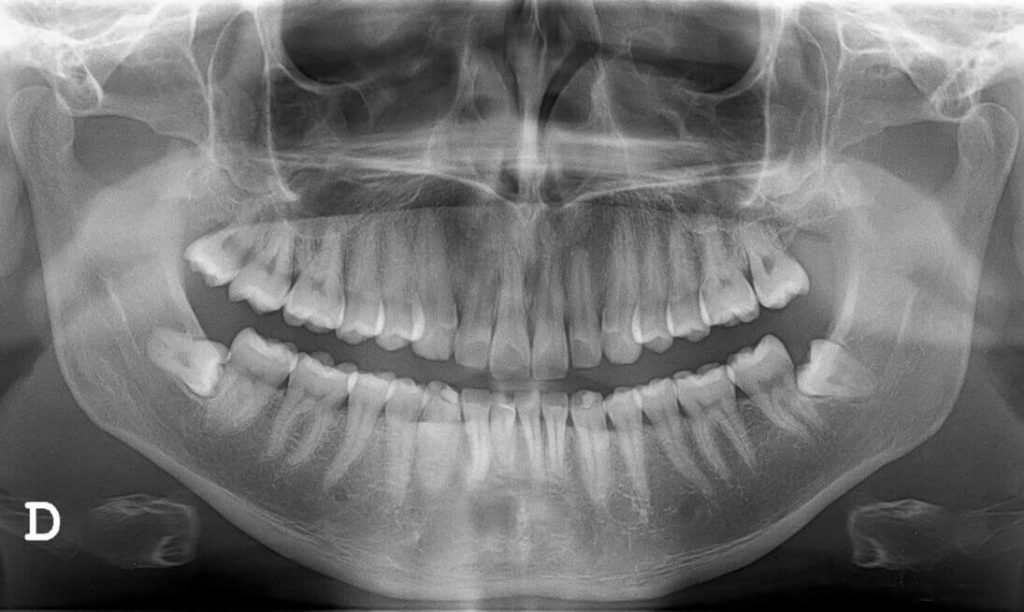

Mit dem digitalen Röntgengerät lassen sich sowohl zweidimensionale Einzelaufnahmen wie auch sogenannte Orthopantomogramme (OPG, PSA) realisieren. Dabei handelt es sich um Panoramaschichtaufnahmen, welche sämtliche Zähne sowie die benachbarten knöchernen Strukturen und Kiefergelenke sowie die Kieferhöhlen abbilden.